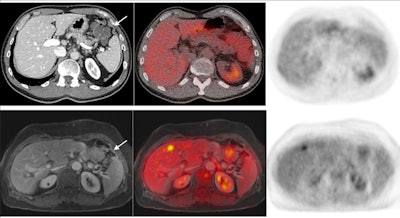

A case of peritoneal thickening not seen on CT and also showing no FDG avidity. Enhancement of pulse-contrast MRI sequences detected peritoneal carcinomatosis, which was later confirmed in surgery. Image courtesy of Dr. Felipe Furtado.Peritoneal carcinomatosis is not uncommon in gastrointestinal cancers, which account for one in three cancer deaths globally, and its detection on imaging is paramount to establish adequate patient management, Furtado said. Ultimately, this study shows that negative findings on PET/MRI can rule out peritoneal carcinomatosis with high confidence, he added.